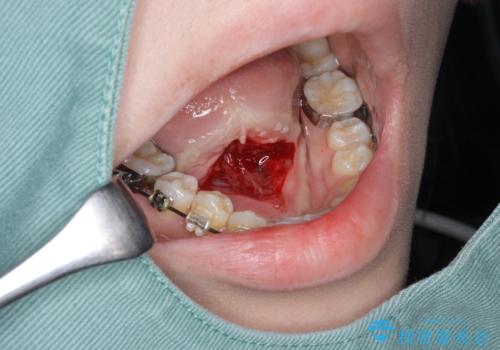

滑舌を改善! 舌小帯の形成術

- 他院での矯正治療中、滑舌の改善を求めて来院されました。

10分程度の短時間で終わる、舌小帯の形成術を行い滑舌の改善を計画します。

外科処置の注意事項(リスク・副作用など)

- 外科手術のため、術後に出血、痛みや腫れ、違和感を伴います